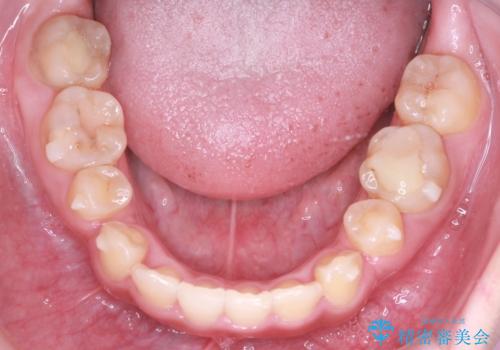

インビザラインによる精密な仕上げ: 全体のがたつきが概ね整った段階で、インビザライン(マウスピース矯正)へ移行しました。透明で目立たないマウスピースを使用しながら、0.1mm単位の細かな歯の配置や、最終的な咬み合わせのバランスを精密に整えていきました。

治療の結果、重度のがたつきは跡形もなく解消され、抜歯したスペースもきれいに閉じました。ワイヤーによる「確実な移動」と、インビザラインによる「緻密な仕上げ」を組み合わせることで、審美性と機能性の両立を叶えた美しい歯並びを実現しました。